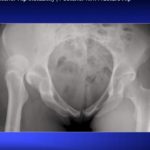

FemoroAcetabular Impingement

Courtesy: Jawahar Pachore, Shrikunj Patel, Ahmedabad, India